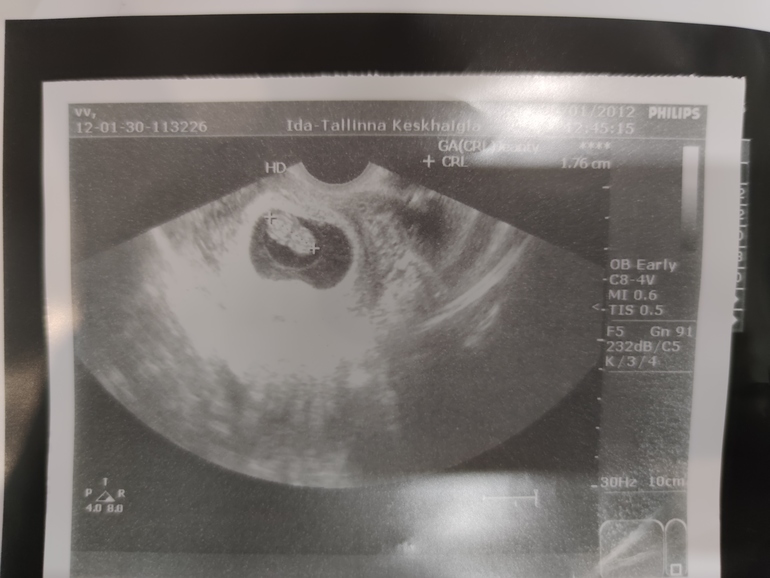

Ну что, кто спец по методу рамзи 😀

Счас дам 3 фото, узи во всех случаях вагинальное, срок по М 7-8 недель :)

старший сын совпал?